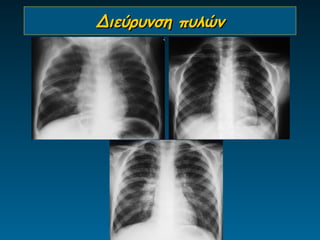

Διεύρυνση πυλών